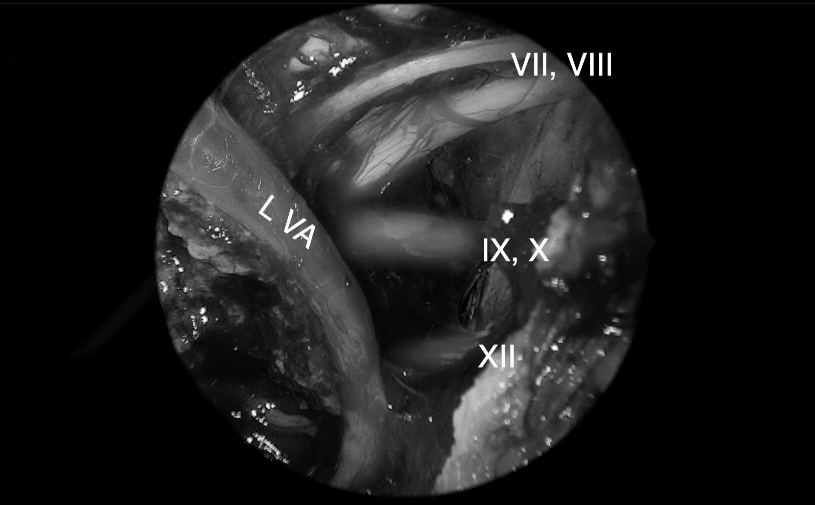

可见周围神经完好。VlI,面神经;VIII,前庭蜗神经;L VA,左侧椎动脉;IX,舌咽神经;X,迷走神经;XII,舌下神经